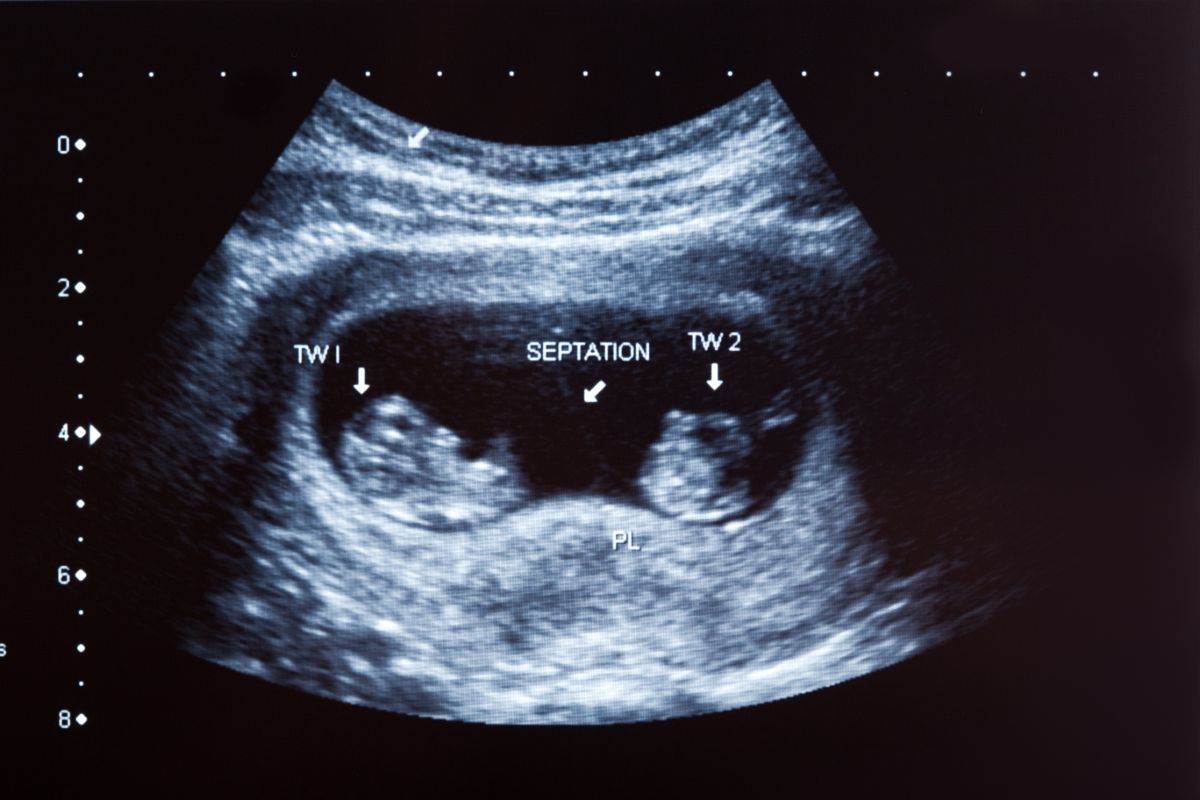

Checks for multiple pregnancies

Ultrasounds can detect your baby’s heartbeat — and show if there is more than one set of heartbeats. If your doctor detects multiple heartbeats, you will likely be having twins, triples, or more babies in this pregnancy.

Carrying more than one baby has special risks, which must be monitored by your doctors regularly. This will enable them to promptly treat you if complications like twin-to-twin transfusion occur.